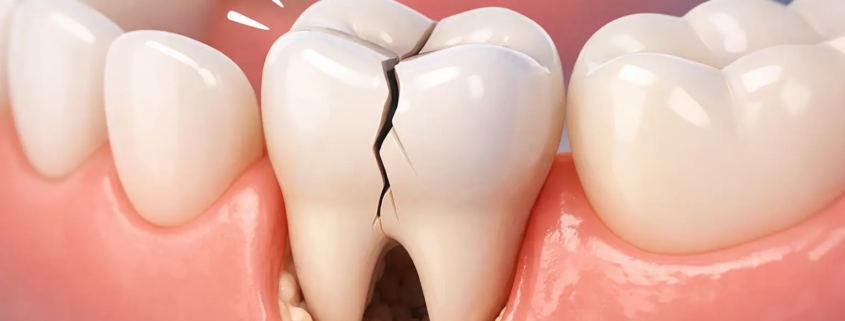

Dent fêlée : douleur à la mastication (symptômes, causes, traitements)

Une douleur à la mastication est l’un des signes les plus fréquents d’une dent fêlée (microfissure ou fissure plus profonde). Le problème, c’est que la dent peut paraître “normale” à l’œil nu, alors que la fissure s’ouvre légèrement sous la pression, déclenchant une douleur vive.

Pourquoi une dent fêlée fait mal surtout quand on mâche ?

Quand vous mordez, la dent subit une pression. Si une fissure est présente, elle peut :

s’ouvrir légèrement, irritant la dentine ou la pulpe

créer un micro-mouvement entre deux fragments de la dent